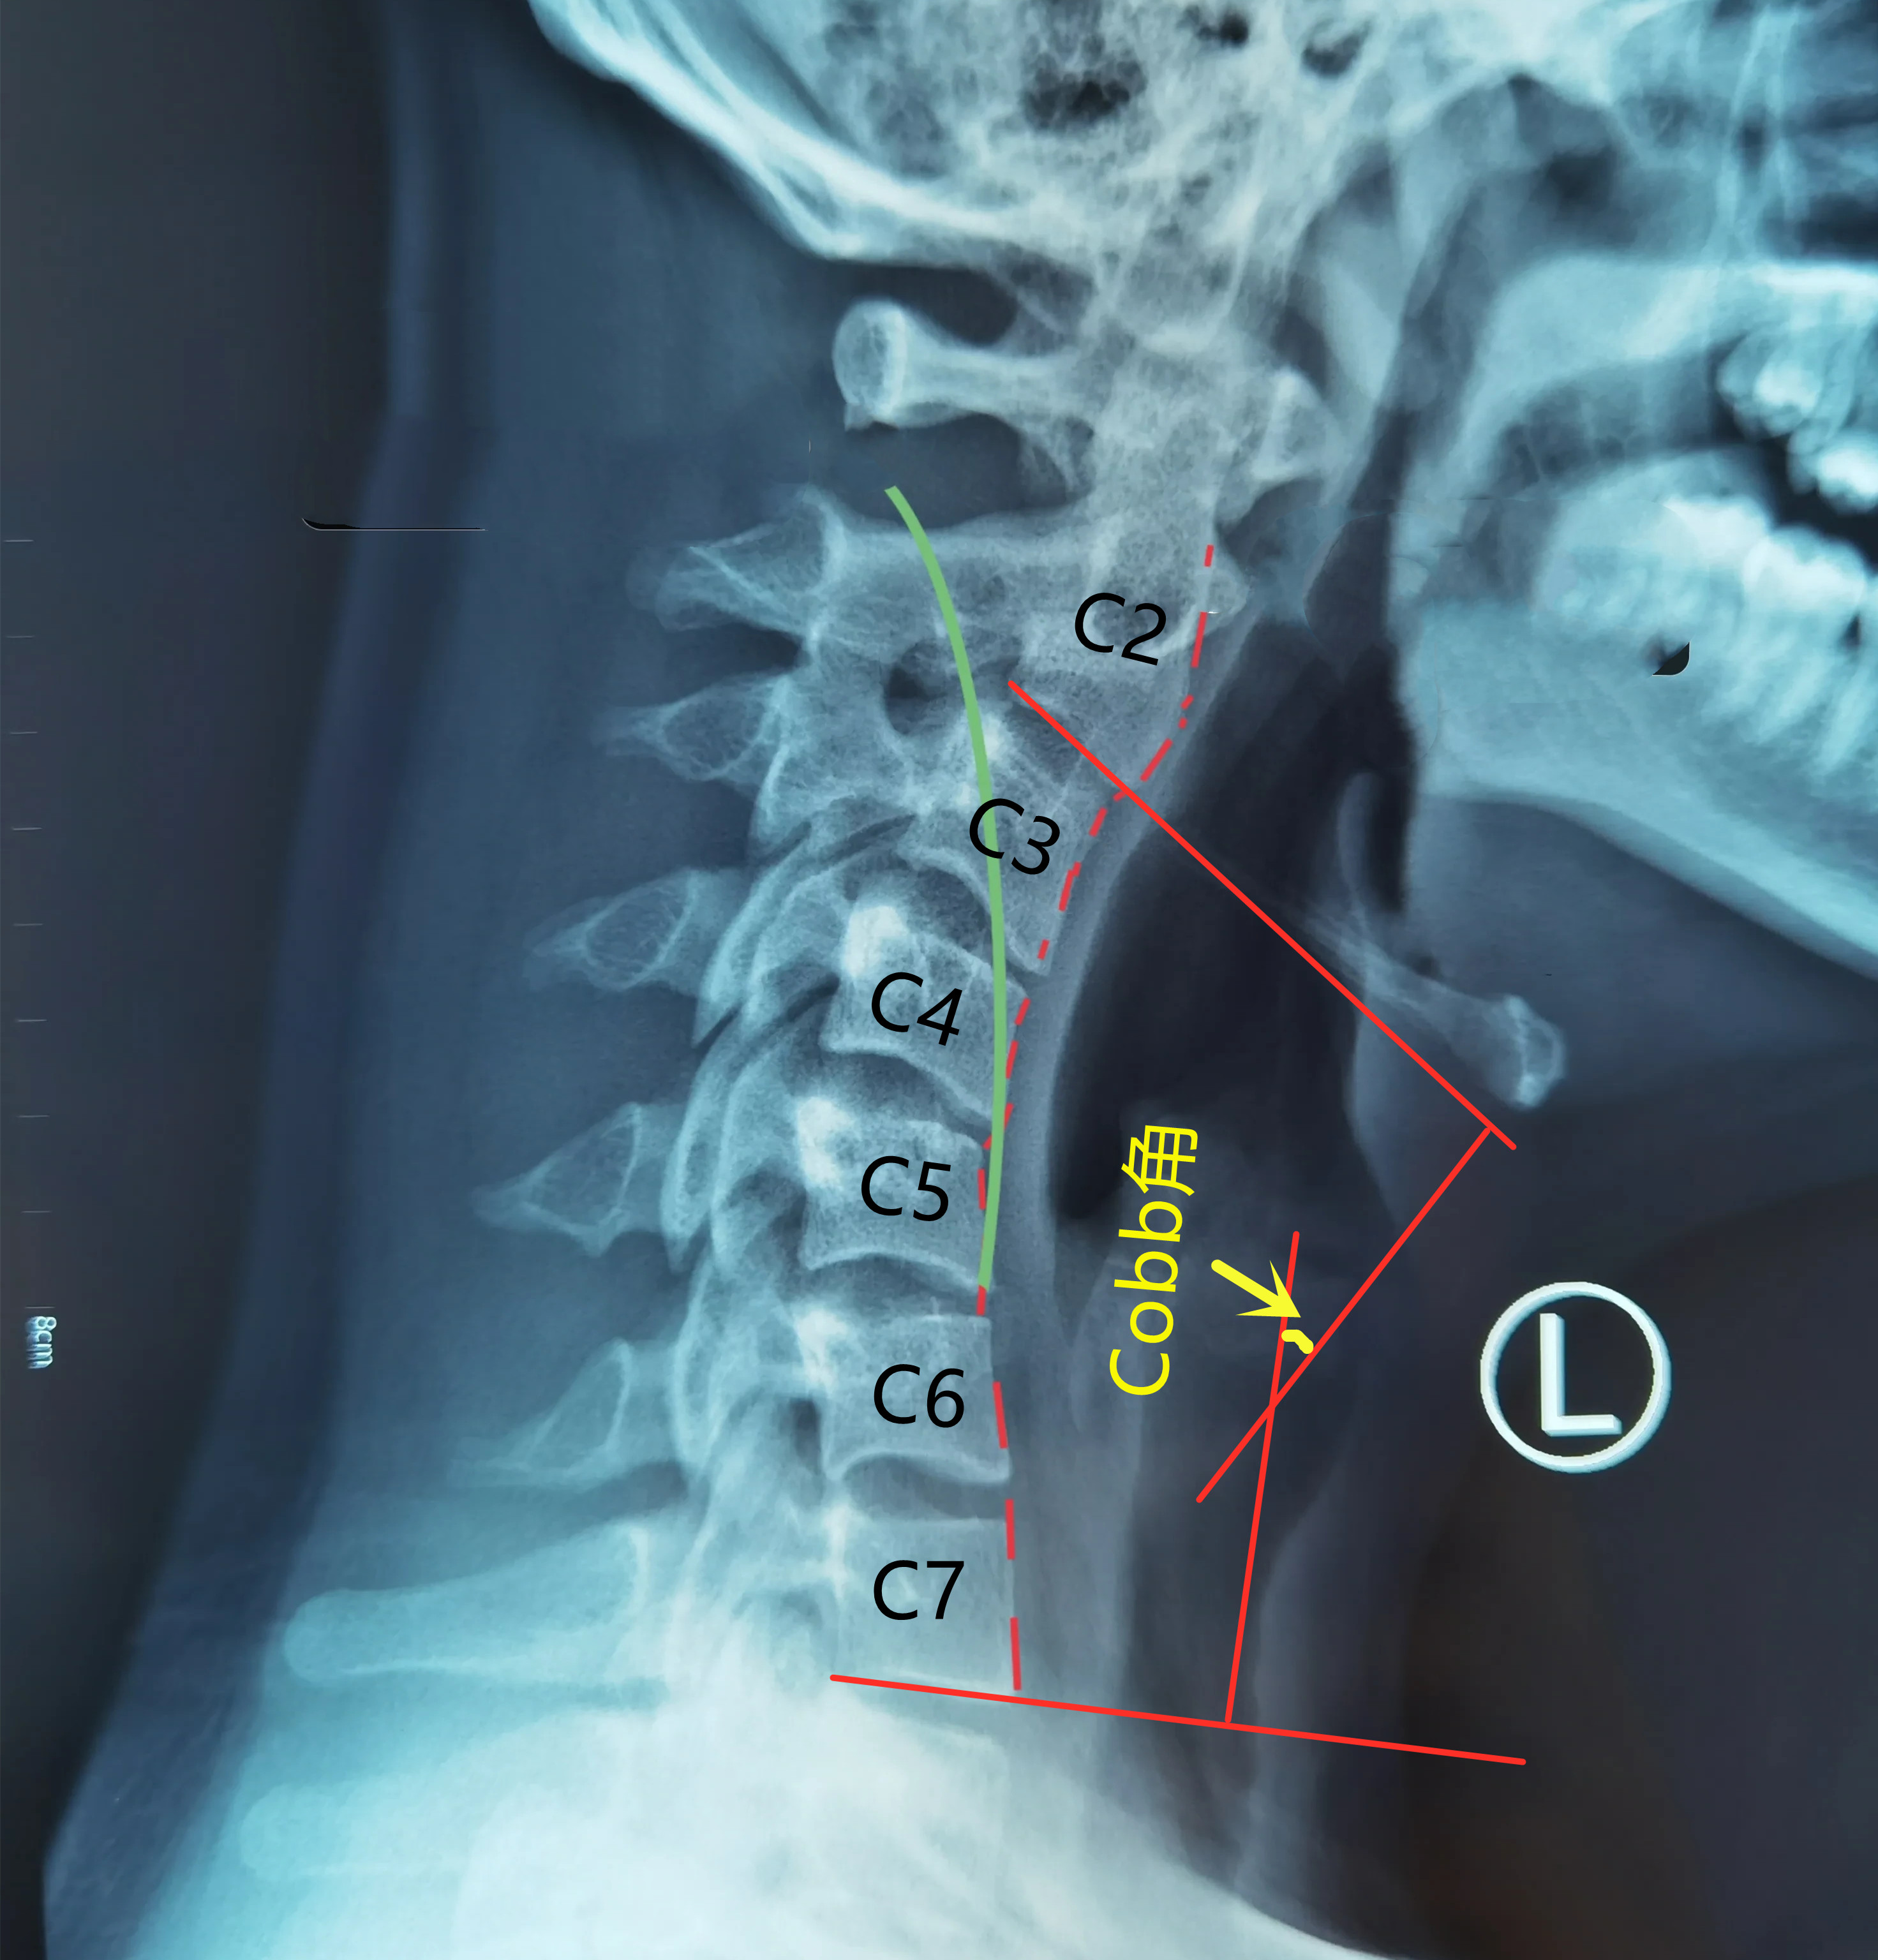

颈椎侧位X线Cobb角的测量方法,正常曲度时Cobb角为负值,约-10°左右

当Cobb角接近0°时,反映我们的颈椎生理前凸基本消失,颈椎呈现一条变直,即发生了颈椎生理曲度变直;当Cobb角大于0°时,表明颈椎曲度发生了反转,由前凸变为后凸,即发生了颈椎反曲。

本患者为19岁电脑资深玩家,颈椎发生反曲(绿线示意正常生理曲度),Cobb角由正常的负值变为正值,约25°